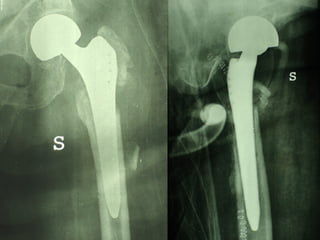

INDICAZIONI COMUNI Fratture sovracondiloidee Fratture intercondiliodee Fratture diafisarie distali PARTICOLARI Fratture con grave osteoporosi Fratture periprotesiche

VANTAGGI CHIRURGIA MININVASIVA Mini Open Inserimento della placca sottocutaneo per scivolamento Viti percutanee Preservazione dei tessuti molli Ridotto danno vascolare Rapida ripresa funzionale

F, 68 y

LISS  NCB

NCB